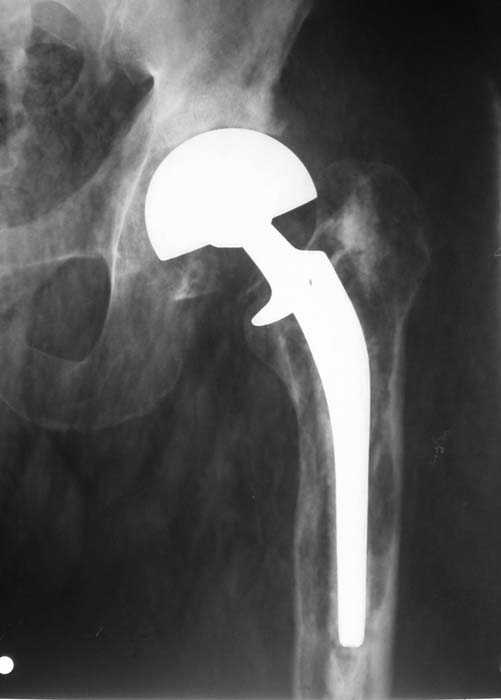

Мужчина, 39 лет.По поводу двустороннего асептического некроза головок бедренных костей последовательно выполнено тотальное эндопроезирование левого (1998 г), затем правого (1999 г) тазобедренных суставов.

22/10/04

С 2001 г отмечает нарастающие боли в левом бедре. Предполагается удаление протеза, удаление цемена из канала бедра, пластика дефекта бедренной кости.

Нет никакого смысла делать операцию в два этапа. С чашкой все понятно - стандартный подход с установкой пресс-фит компонента. На бедре имеет

место перипротезный перелом В3 типа - т.е. перелом вокруг ножки с ее нестабильностью на фоне выраженного остеолиза. Решение - доступ к каналу

через перелом с удалением самой ножки, костного цемента и рубцовых тканей. Установка ножки дистальной фиксации (типа Solution), длину ножки

надо определить по шаблону. Минимальный контакт ножки с интактной костью - 6-8 см. Фрагменты проксмального отдела собираются на ножке

эндопротеза, дефекты костной ткани заполняются чипсами (аллографт) и фиксируются кортикальными аллографтами, уложенными дополнительно по типу

"вязанки хвороста" серкляжом. Мы имеем 8 или 10 подобных наблюдений и результатами довольны.